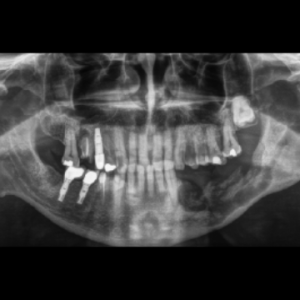

La sobrecarga provocada por el bruxismo puede afectar a la supervivencia de los implantes dentales. El objetivo del presente estudio fue evaluar el fracaso del implante y la pérdida ósea marginal...

La estabilidad del hueso marginal y del tejido blando alrededor de los implantes dentales se ha establecido como la principal característica para asegurar la salud del implante.La condición...

Los implantes utilizados para reemplazar los dientes molares presentan problemas de distribución del espacio y contornos de la corona que son exclusivos de estos sitios. Debido a que el diámetro...

La investigación tuvo como objetivo evaluar el tratamiento de dentaduras con implantes maxilares soportados por barras cuando se apoyan en cuatro o seis implantes después de 10 años.Los pacientes...